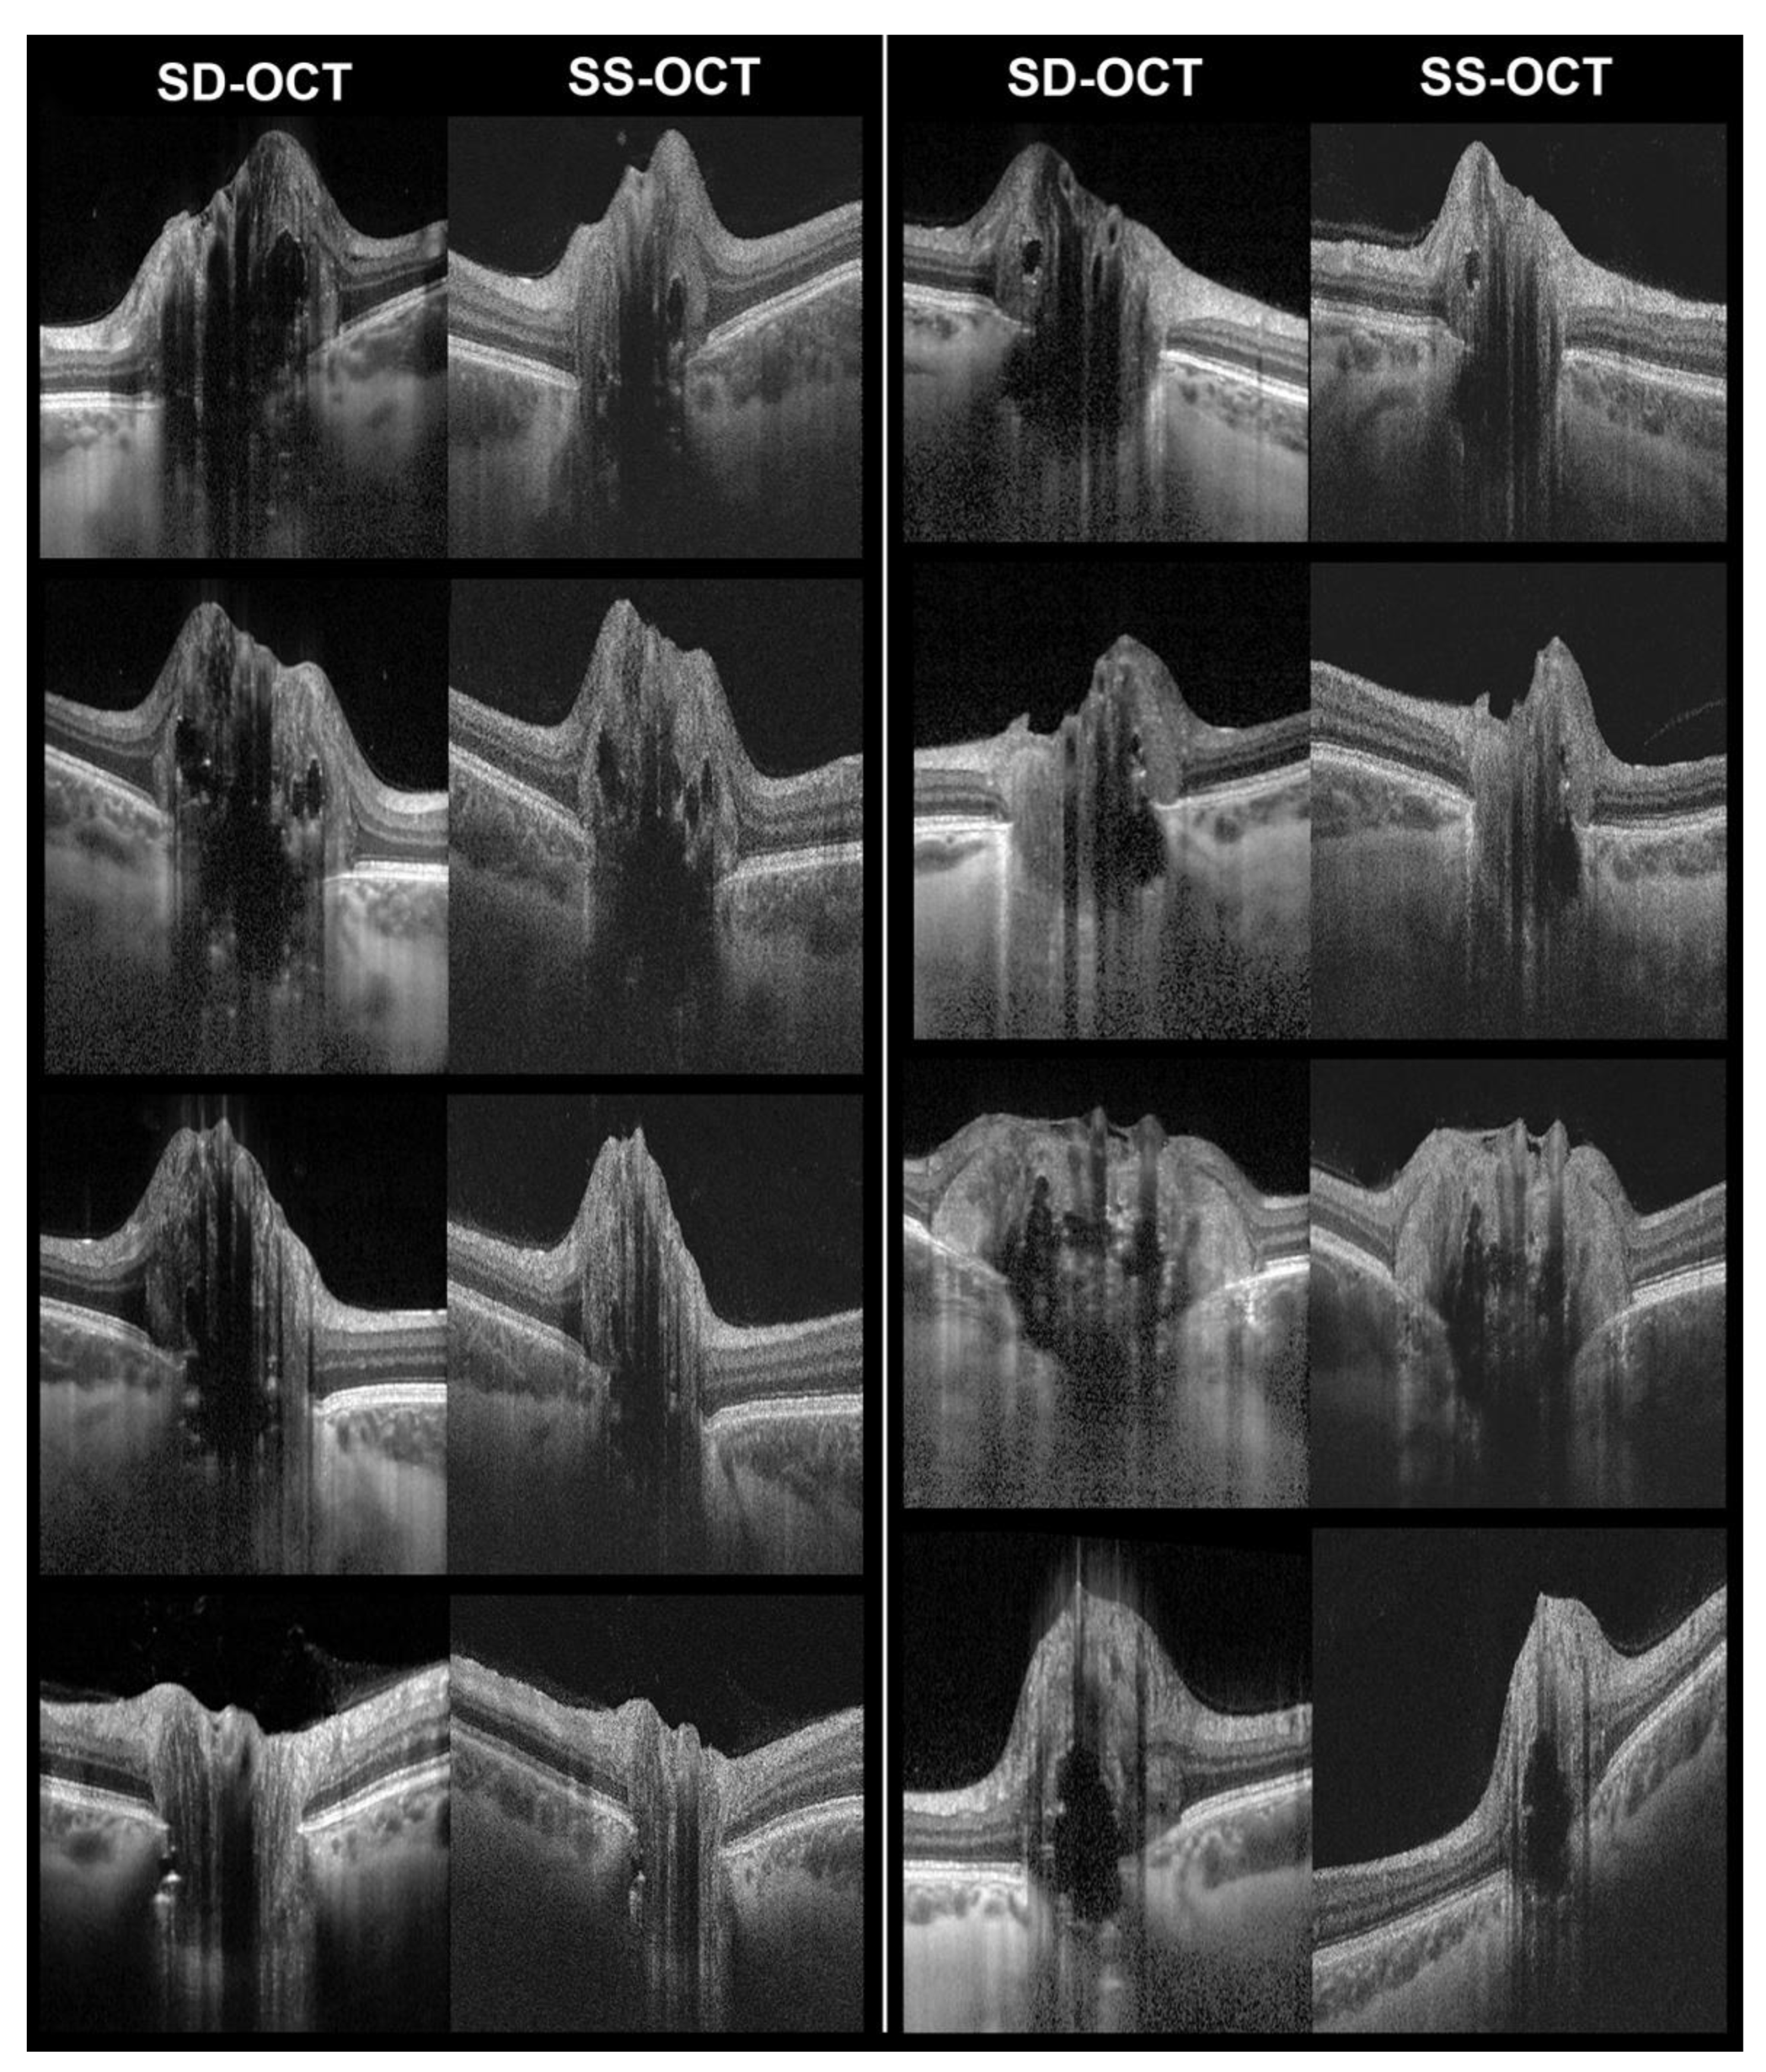

Figure 2. Examples of corresponding B-scans with enhanced depth imaging spectral-domain OCT (SD-OCT) and swept-source OCT (SS-OCT). Images show optic disc drusen (hyporeflective bodies with hyperreflective margins) and some associated features, such as hyperreflective lines and PHOMS.